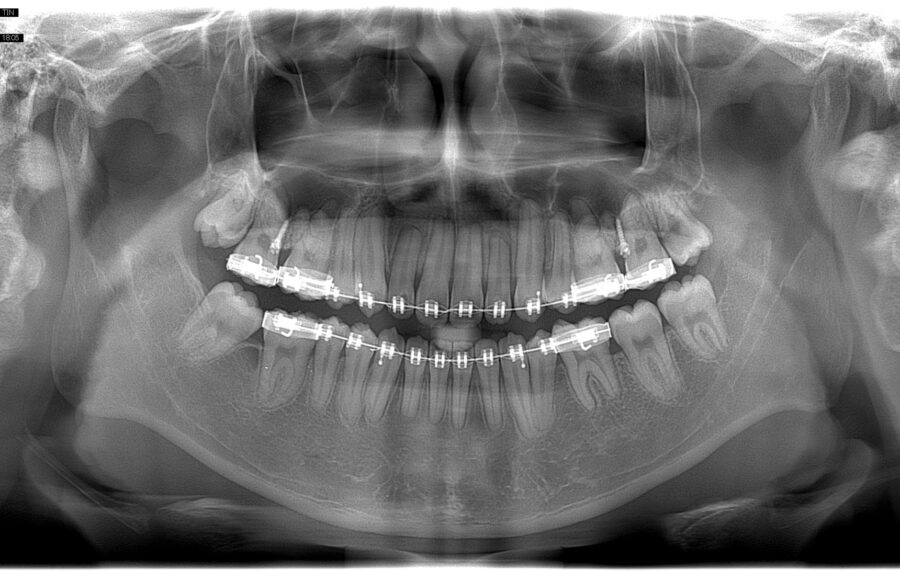

Phát hiện tổn thương nghiêm trọng tiềm ẩn ở răng cối hàm dưới

Sự tổn thương ở các răng cối hàm dưới